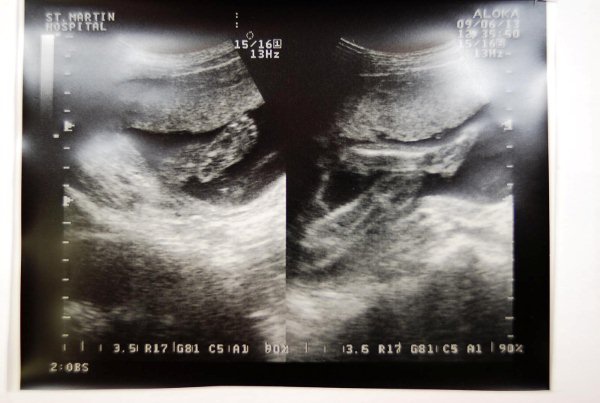

又過了四週來到6/13例行產檢(滿23週) 體重穩定成長2公斤(平均一週0.5公斤)

根據醫生判斷及超音波儀器計算(頭圍 腹圍及腳長) 北鼻約有730公克重 比書上所說550公克還多 自己也有些嚇一跳 還擔心北鼻會不會長太快了(即便大家都看不出我肚子有六個月大了)...照片中北鼻的腳丫子很清楚喔 感覺上腳也蠻長的ㄛ